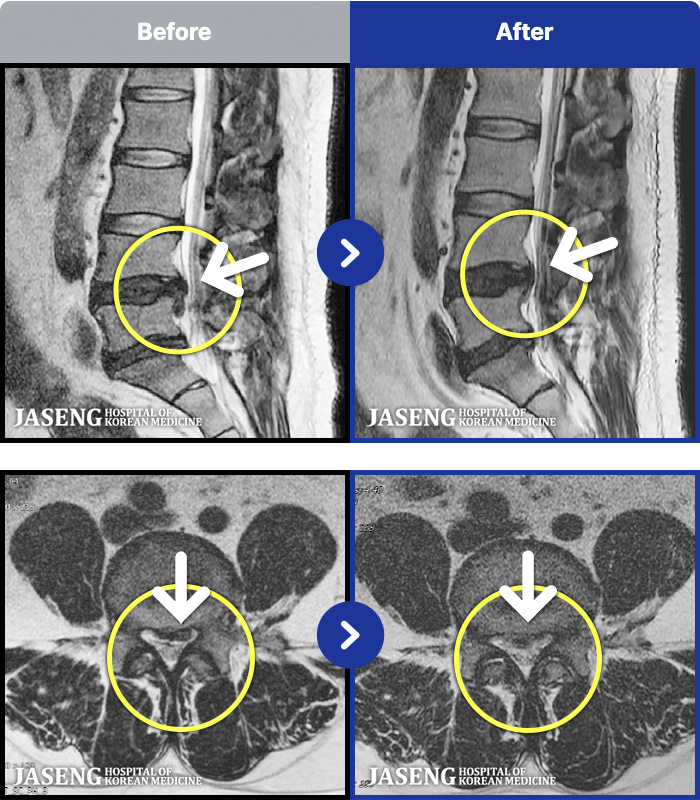

1,299 MRI ũ ʸ Ȯϼ.

Ϻ ߿ Ͽ, ٸ ٱ Ƹ ݵǾϴ. |